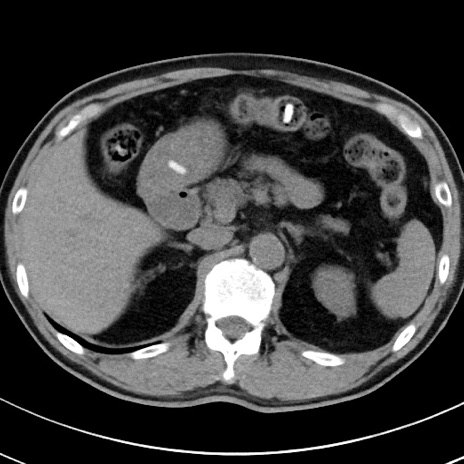

【腹部TIPS】症例29 参考症例 CT(横断像)

症例

70歳代男性